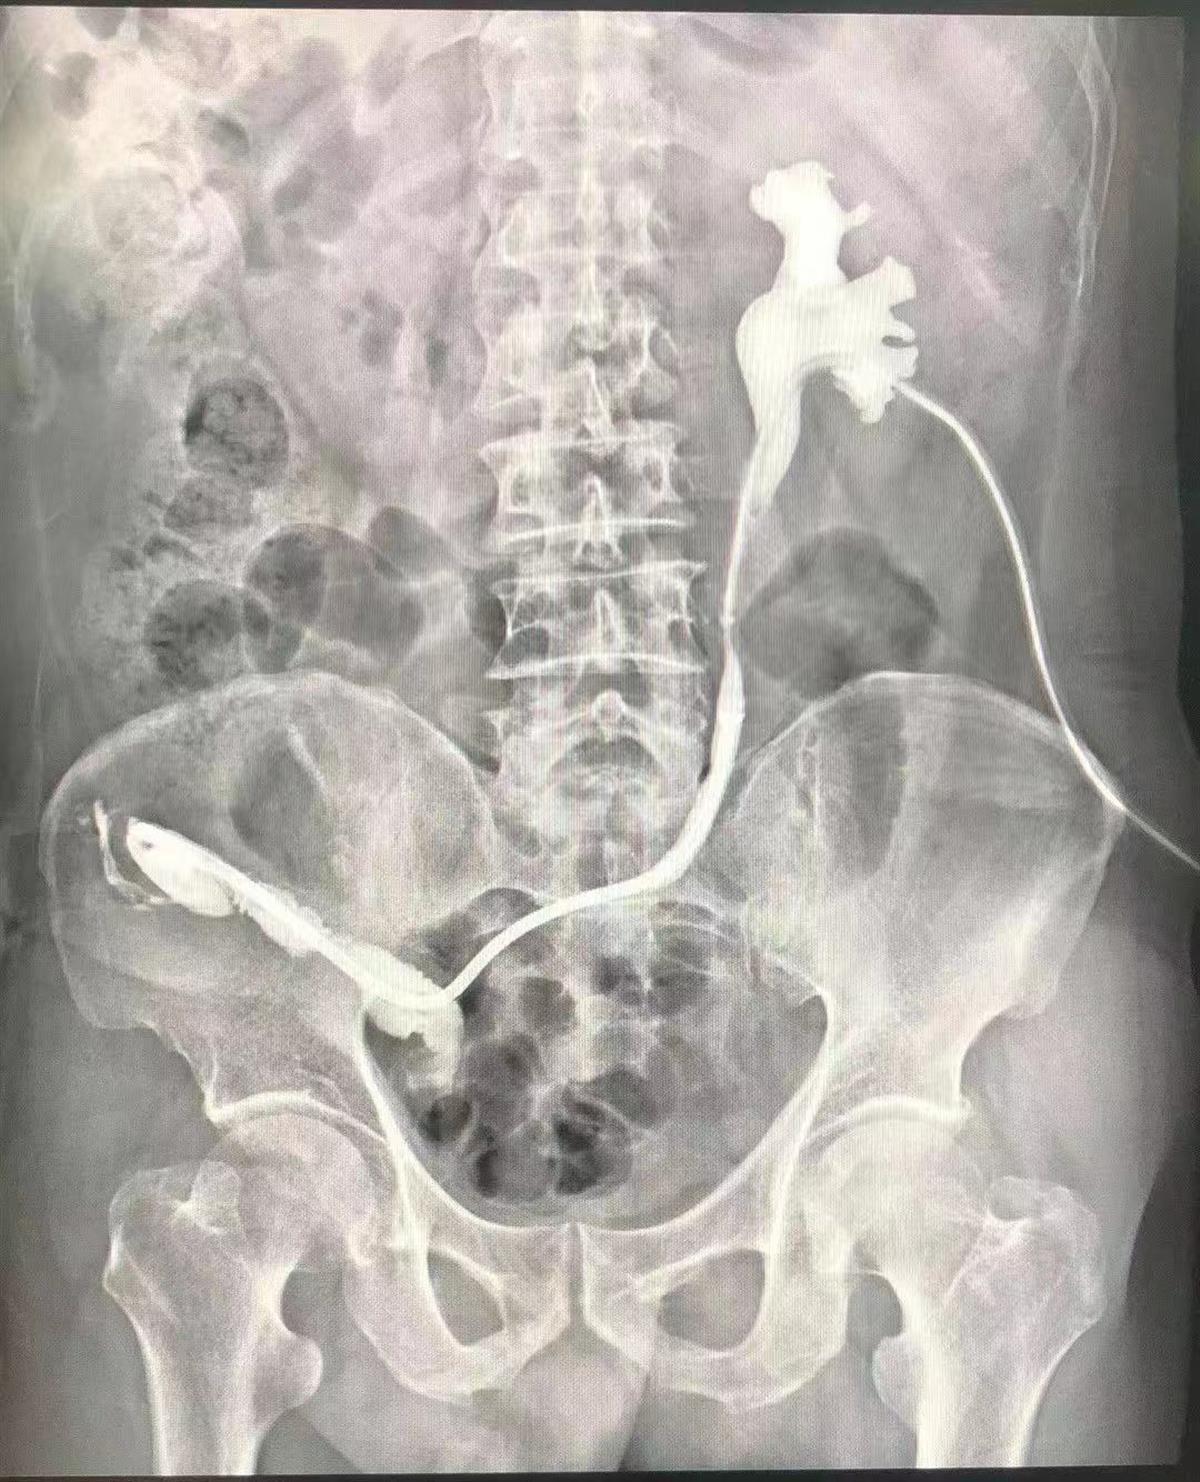

患者影像资料(通讯员供图)

在完善术前检查后,该院泌尿外科团队进行术前讨论,根据老人的身体条件制定了温控记忆合金输尿管支架治疗输尿管——回肠吻合口狭窄的手术方案,手术由该院院长曾晓勇教授主刀,利用温控记忆合金输尿管支架技术,结合输尿管软镜技术,为张爹爹解除了输尿管——回肠吻合口狭窄,解决了困扰他多年的肾造瘘问题。目前,张爹爹恢复良好,并于9月6日顺利出院。